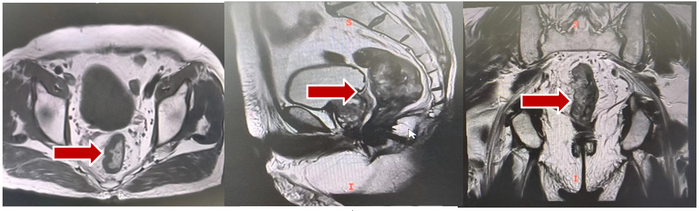

盆腔MRI(2021年04月26日):1.直肠管壁及周围改变,考虑中位直肠癌:T4aN2,CRM(阳性),EMVI(阳性)(图1)。

图1 2021年04月26日盆腔MRI

2023年1月、4月复查胸部CT:肺部病灶部分缩小;上腹部MRI:肝V、VII段异常信号影(较大者大小2.5*1.6cm),较前变化不大,右侧肾上腺转移病灶增大(图11)。

图11 2023年1月、4月胸部CT及上腹部MRI